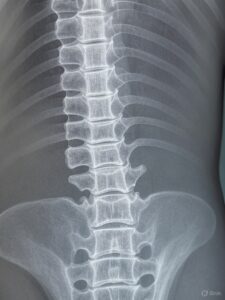

子供の側弯症は、主に成長期に背骨が曲がる病気で、

左右の肩の高さの違い、肩甲骨の突出、ウエストの非対称性などの症状が見られます。

治療法は進行度によって異なり、軽度なら経過観察、中等度なら装具治療、

高度の場合は手術が検討されます。

子供の側湾症は「タイプ」が個人差があります